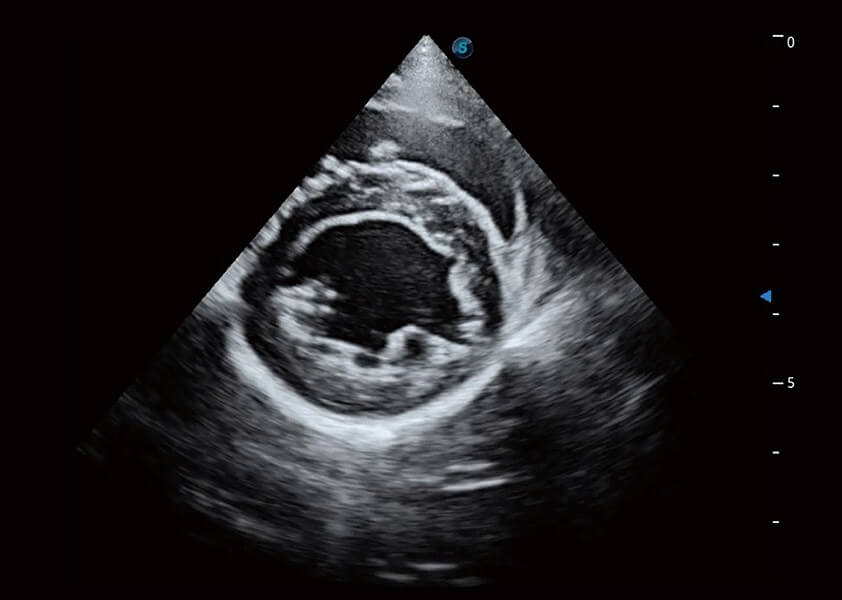

ProPet 60 作为一款高端台式动物超声设备,为动物医生的日常诊断提供了一系列贴合动物临床需求、解决临床实际问题的高级成像功能。凭借全系列高清探头,满足医生对腹部、心脏、生殖、浅表、肌骨等成像的所有需求,切实帮助您提升检查效率,提高诊断信心。

动物是人类最亲密的朋友和最值得信赖的伙伴。狗万官方网站也一直致力于探索动物专用的超声影像解决方案。 全新推出的ProPet系列,是狗万官方网站在动物超声影像智能化、专业化、精准化的一次跨越式革新。动物不能用言语来表述自己的不适,通过超声影像,ProPet系列搭建了动物医生与不同物种沟通的“桥梁”,为动物医生注入了“治愈之力”。